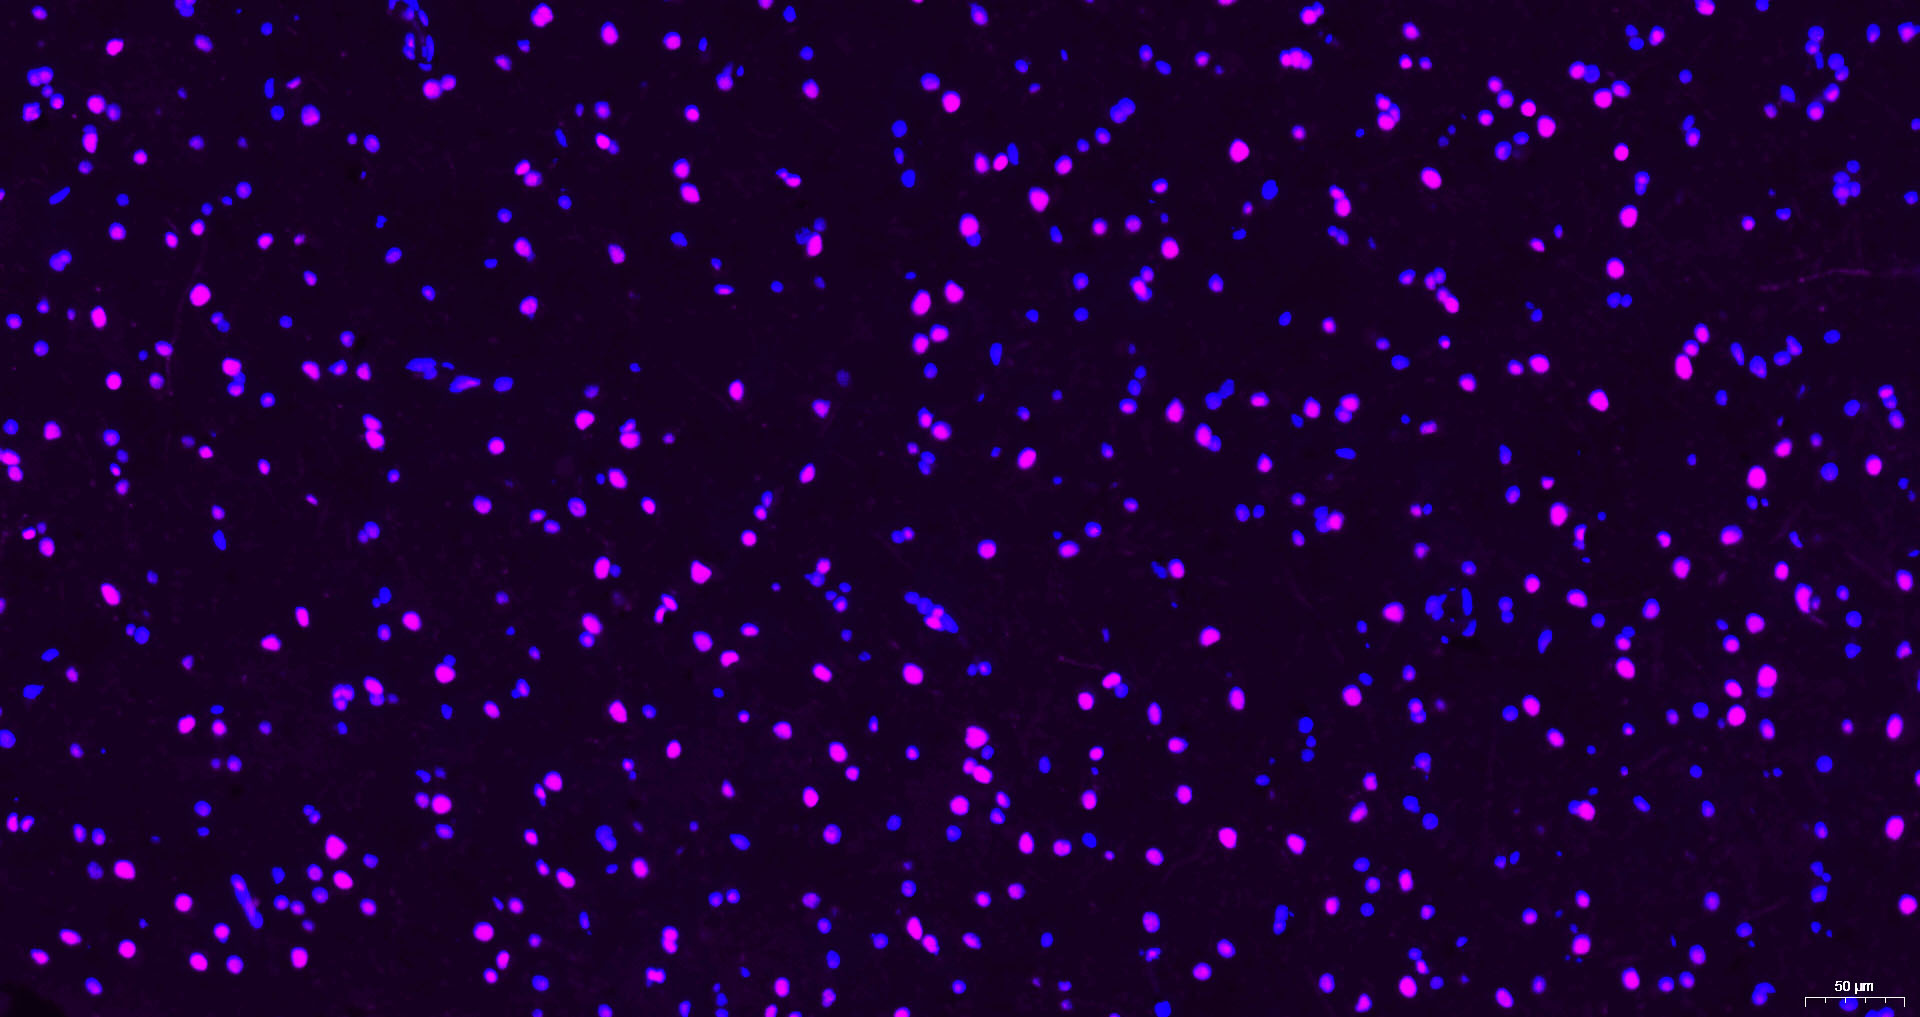

Paraformaldehyde-fixed, paraffin embedded Human Cerebrum; Antigen retrieval by boiling in sodium citrate buffer (pH6.0) for 15 min; Antibody incubation with Histone H3 Monoclonal Antibody, Unconjugated (bsm-33042M) at 1:200 overnight at 4°C. Followed by conjugated Goat Anti-Mouse IgG antibody (Purple, bs-0296G-Cy5), DAPI (blue, C02-04002) was used to stain the cell nuclei.